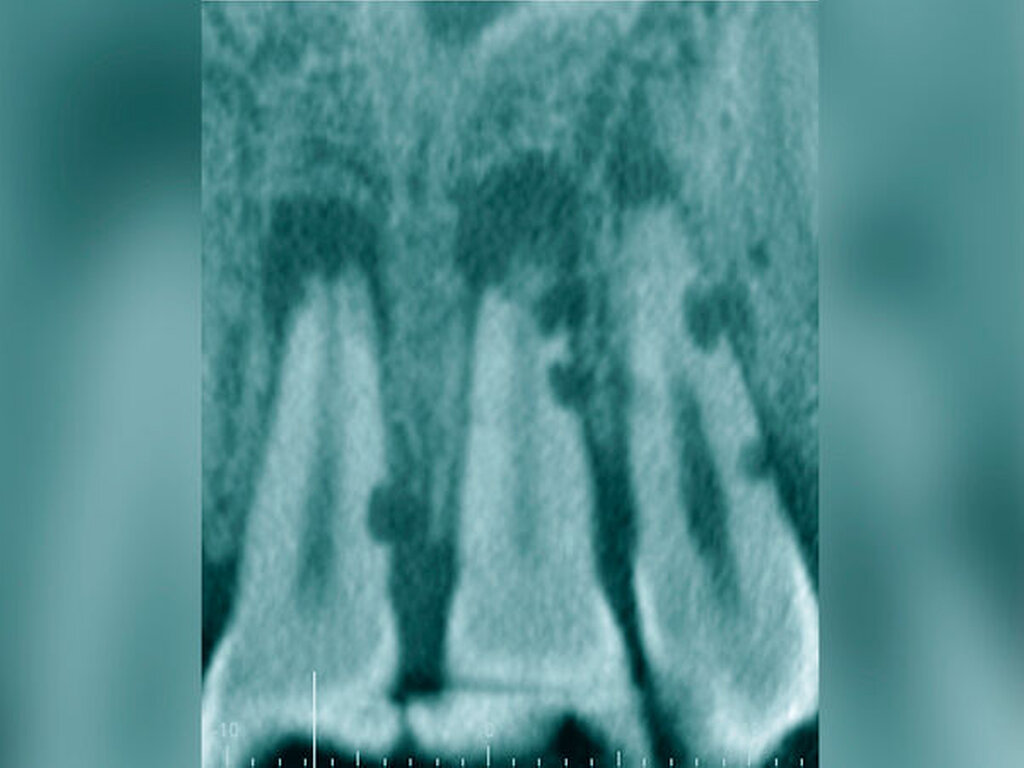

Jede erforderliche endodontische Revision ist eine Summe von mehreren endodontischen Problemstellungen, die die Grenzen einer bisher unter normalen zahnärztlichen Bedingungen möglichen Wurzelkanalbehandlung aufzeigt. Eine Korrektur ist meist nur unter Zuhilfenahme spezieller Hilfsmittel und einer optimalen optischen Vergrößerung möglich (Abbildung 5) [Imura et al., 2007; Naito, 2010].